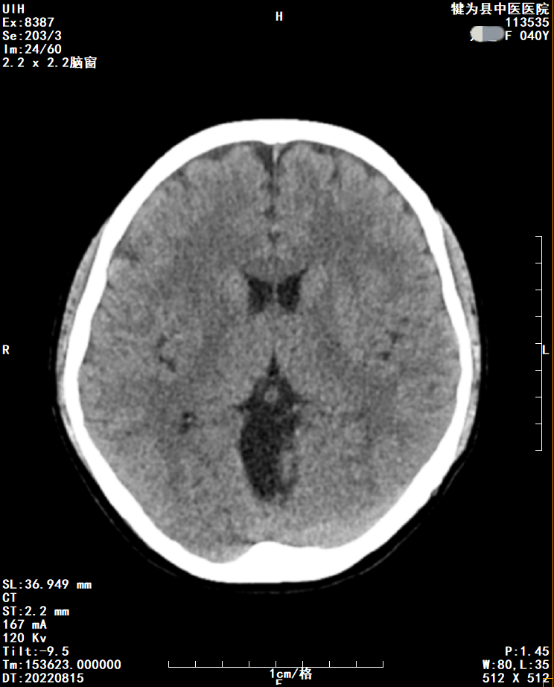

接下来看看CT图像

DR胶片为什么分尺寸【影像科普】教你识别影像胶片的四角信息_https://www.jmylbn.com_新闻资讯_第7张

基本信息同DR图像相同,需要特别指出的是右下角的ST代表CT图像层厚,数值越小密度分辨率越高,空间分辨率会降低。